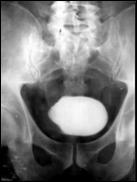

4.1. Radiografia renovezicala simpla si UIV raman examenele de baza pentru diagnosticul etiologic al oricarui pacient cu hematurie. Tumorile vezicale au drept semn radiologic cardinal imaginea lacunara pe cistograma urografica. Tumorile infiltrative pot induce modificari ale supletii peretelui vezical, care devine rigid, inextensibil, retractat etc. in zonele patologice. Ureterohidronefroza sau rinichiul mut sunt rezultatele invaziei si obstructiei ureterelor intramurale induse de tumorile solide, infiltrative (Fig.27,28,29).

Figura 28. Imagine

lacunara de 2,8/2 cm, in aria vezicii urinare, sugerand tumora

vezicala.

Figura 33. a) Imagine lacunara voluminoasa, ocupand

hemivezica dreapta; rinichi drept mut UIV; b) Imagine lacunara in hemivezica

dreapta; c) Rigiditate la

nivelul hemivezicii drepte; d) Cistouretrografie intramictionala

demonstrand imagine lacunara in hemivezica stanga.